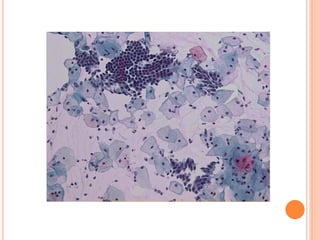

O hormônio que atua na maturação é o estrogênio. As células encontradas no Papanicolaou que sofrem a ação do estrogênio são as células escamosas. Estas células podem ser observadas no Papanicolaou principalmente na fase proliferativa do ciclo menstrual.